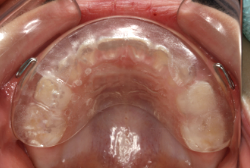

ネックバンドを1年半使用して、上顎大臼歯が十分後ろに下がったところで、裏側にリンガルアーチという固定のワイヤーを取り付けて、新しく生じた隙間が狭くならないよう「保隙(ほげき)」という処置をして、永久歯が生えそろうまで待機中の様子です。配列全体に隙間が生じているのがお分かりいただけると思います。これだけの隙間が確保できていれば、抜歯をしなくても、あとで上の前歯を内側に理想的な角度で引っ込めることができます。このように完全に永久歯列になる前に、十分な隙間が確保できるかどうかが、非抜歯で矯正できるかどうかの分かれ目になります。